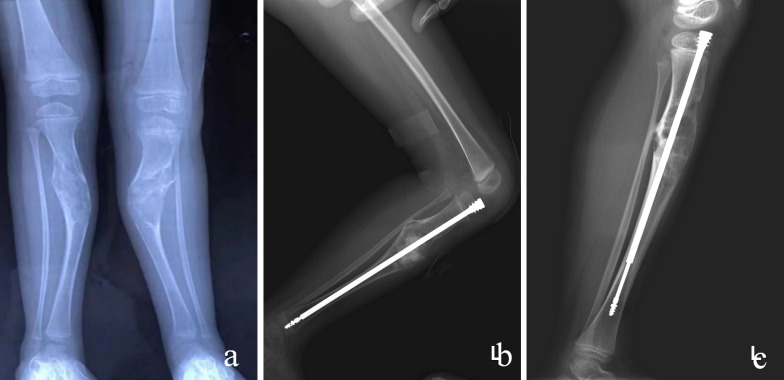

Materials and methods: This retrospective analysis included 28 patients (30 extremity) with severe pain, pathological fractures, angular deformities, or extensive cortical bone involvement. On the basis of the surgical approach, patients were divided into four groups: group 1, curettage, allograft, and plate fixation for six patients (six extremity); group 2, elastic stable intramedullary nailing fixation for six patients (six extremity); group 3, Fassier-Duval telescopic system fixation for eight patients (nine extremity); and group 4, interlocking intramedullary nail for eight patients (nine extremity).

Results: All patients achieved bony union and pain alleviation with no recurrence of deformities. The refracture rate during the follow-up was zero cases (0%; group 1) versus one (16.7%; group 2) versus zero (0%; group 3) versus zero cases (0% group 4) (p > 0.05). Instances of internal fixation loosening were zero cases (0%; group 1) versus zero (0%; group 2) versus five (55.6%; group 3) versus zero cases (0%; group 4) (p < 0.05). The musculoskeletal tumor society (MSTS) scores of the four groups were 27.5 (group 1) versus 27.7 (group 2) versus 26.3 (group 3) versus 28.7 (group 4) (p < 0.05).